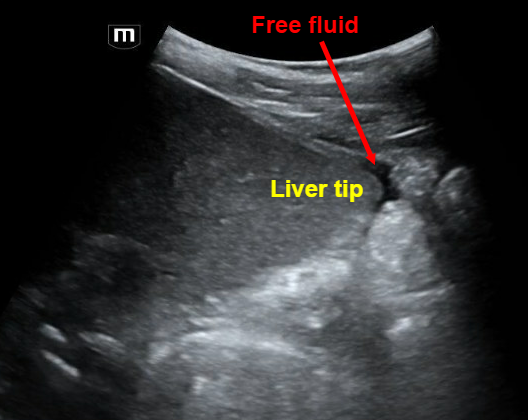

The team did a FAST and here are some labeled images from their respective clips:

Clip 2 shows a RUQ view with the liver that appears to have a heterogenous mass.

• RUQ view is most sensitive – Look at diaphragm → Morison’s → inferior kidney pole with fluid often first at liver tip